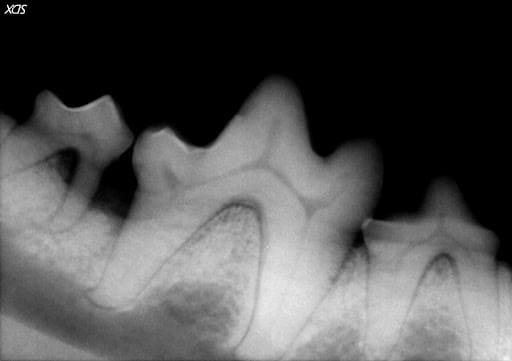

Moderate attachment loss of the tissues around a tooth requires more aggressive tactics. Open root planing with guided tissue regeneration is a procedure that serves this purpose. In guided tissue regeneration, a gingival flap is created to expose the root surface for cleaning and debridement due to the depth of the attachment loss. Once the infected tissue is removed and the root surface meticulously cleaned, different types of bone graft material are placed in the deep pocket and the gingival flap is surgically closed. This procedure allows for osseous (bone) regeneration around the root structure and regrowth of the periodontal ligament. This procedure also carries an excellent long term prognosis when performed by a board-certified veterinary dentist.

Figure 5. A large mandibular molar in a dog with severe bone loss from periodontal disease. Unfortunately, the small molar to the left could not be saved and was surgically extracted.

Figure 6. The same tooth 6 months after an open root planing and guided tissue regeneration procedure. The lost bone and periodontal ligament have been regenerated.